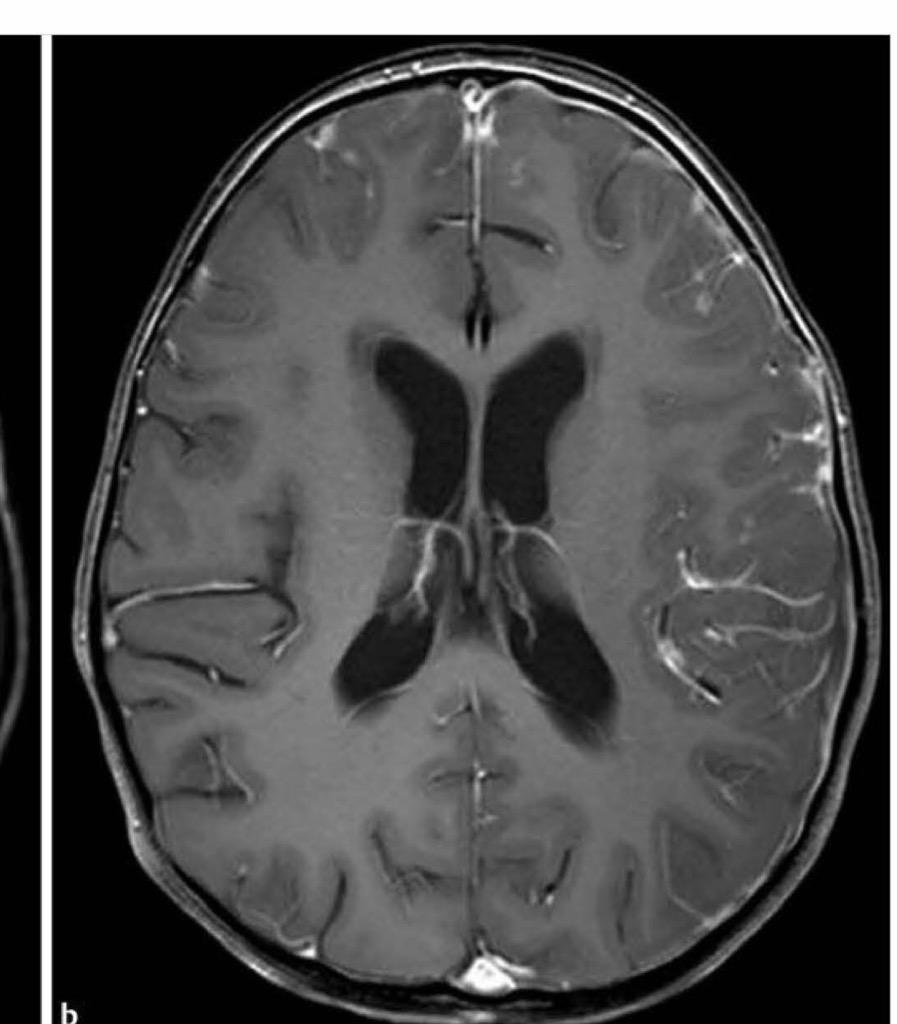

Bacterial Meningitis CT Scan Ddx Meningitis Diagnoses to consider aside from meningitis include the following: aseptic meningitis is the most common form of meningitis with an annual incidence of 7.6 per 100,000 adults. meningitis is inflammation of the subarachnoid space, the fluid bathing the brain (between the arachnoid and the pia mater; the pathogenesis, epidemiology, treatment, prognosis, and prevention of acute bacterial meningitis. Ddx Meningitis.